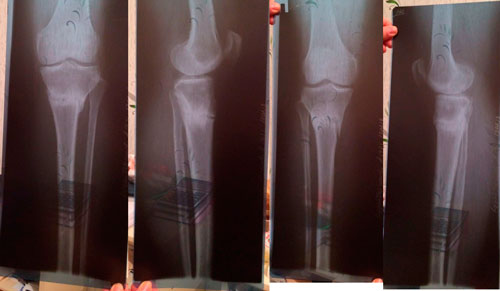

рентген в 3 месяца, после снятия аппаратов.

Советы: раз в пол года старайтесь принимать биодобавки (в основе Кальций, Магний), женщинам за 40...

После 40 у женщин в этом возрасте затухает гормональная функция и возникает опасность для костной системы – костная масса уменьшается с каждым годом почти на 1%. Необходима консультация врача гинеколога, который поможет подобрать гормоно- заместительную терапию для поддержания здорового баланса и продления молодости организму. 094f316296.gif